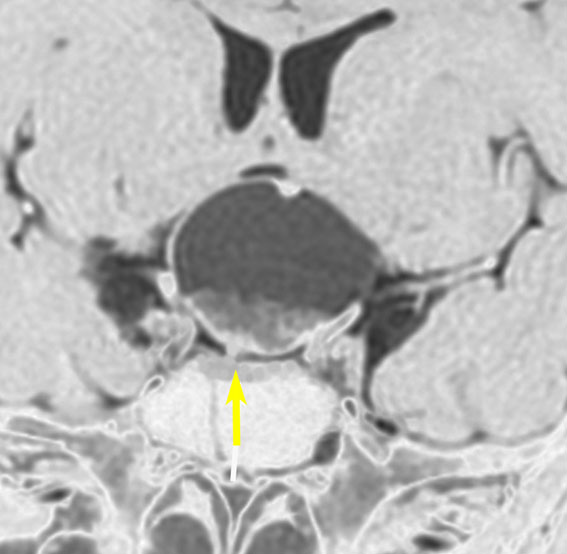

7歳の子が視力障害で発症しました。両耳側半盲という症状です。典型的な鞍隔膜下頭蓋咽頭腫です。ガドリニウム造影剤を入れないMRIでみえる,黄色い矢印の先の白い高信号は抗利尿ホルモンです。ですから下垂体機能もまだ残っていて,尿崩症はありません。視力障害が戻らないことがあるのでなるべく早く,経鼻的な手術で摘出した方がいいものです,簡単 o(^-^)o